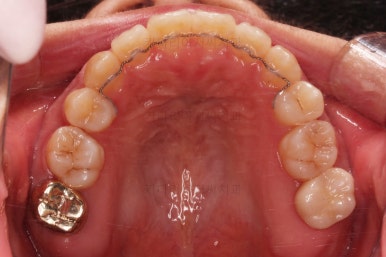

초진 시 입안의 모습입니다.

그냥 봐도 뭔가 애매함이 있죠?

중앙선이 맞지 않고, 교합이 떠보이는 양상이네요.

윗니는 좌측 작은 어금니가 한 개 모자랐고 아랫니는 앞니 하나가 모자라네요.

그런데 앞니는 아랫니가 1개 모자란 채로 교합이 맞춰져서 윗니가 하나 부족한 채로 애매한 상태였어요.